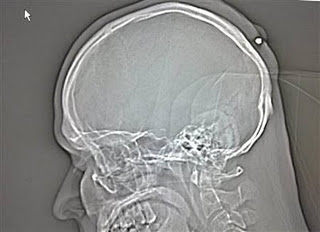

2. Peluru 5 tahun dalam kepala

Seorang pria yang hidup di Jerman hidup dengan normal dan baik-baik saja selama lima tahun tanpa menyadari ia telah ditembak di kepala. Peluru kaliber 0,22 ditemukan ketika orang itu pergi ke dokter untuk memiliki apa yang ia pikir merupakan kista . Yang dia ingat adalah bahwa ia telah menerima pukulan ke kepala sekitar tengah malam di sebuah pesta Tahun Baru tahun 2004 tapi sudah lupa tentang hal itu karena ia �sangat mabuk.�